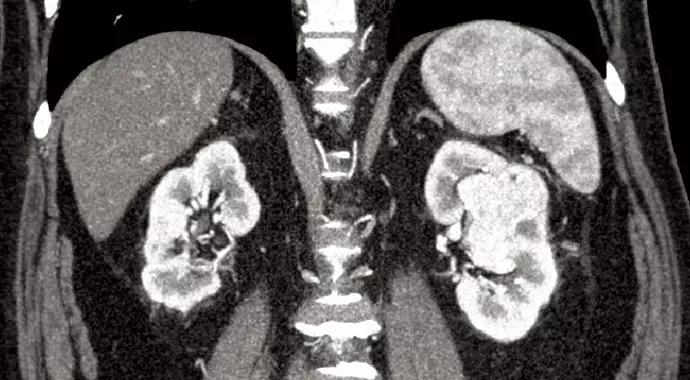

Pathology on the biopsy specimen indeed demonstrated clear cell renal cell carcinoma, and the patient underwent treatment with two cycles of sunitinib to attempt neoadjuvant downsizing. Re-evaluation of the renal mass with CT following treatment revealed a decrease in size of the mass from 5.4 cm to 3.9 cm (Figure 2). Despite the categorization as a complex renal mass, it was believed that nephron-sparing surgery would be more feasible if this tumor were significantly smaller.

Stein-fig2

Figure 2. After neoadjuvant treatment with sunitinib, the renal mass decreased in size to 3.9 cm.